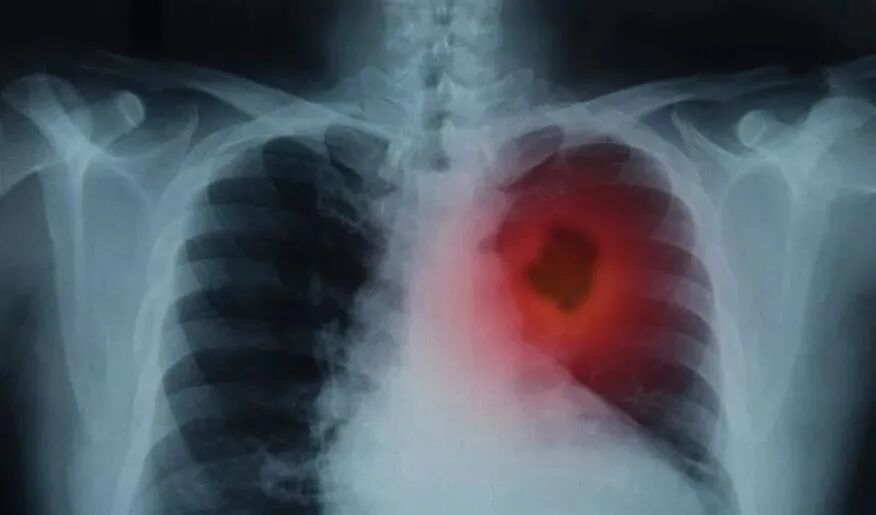

降压药,致癌风波

7952例肺癌病例,致癌率高于其他类型药物14%,

服用五年致癌率22%,服用十年致癌率31%。

在此期间,在这些高血压患者中

确诊了7,952例肺癌

(每1000人中1.3例/年)。